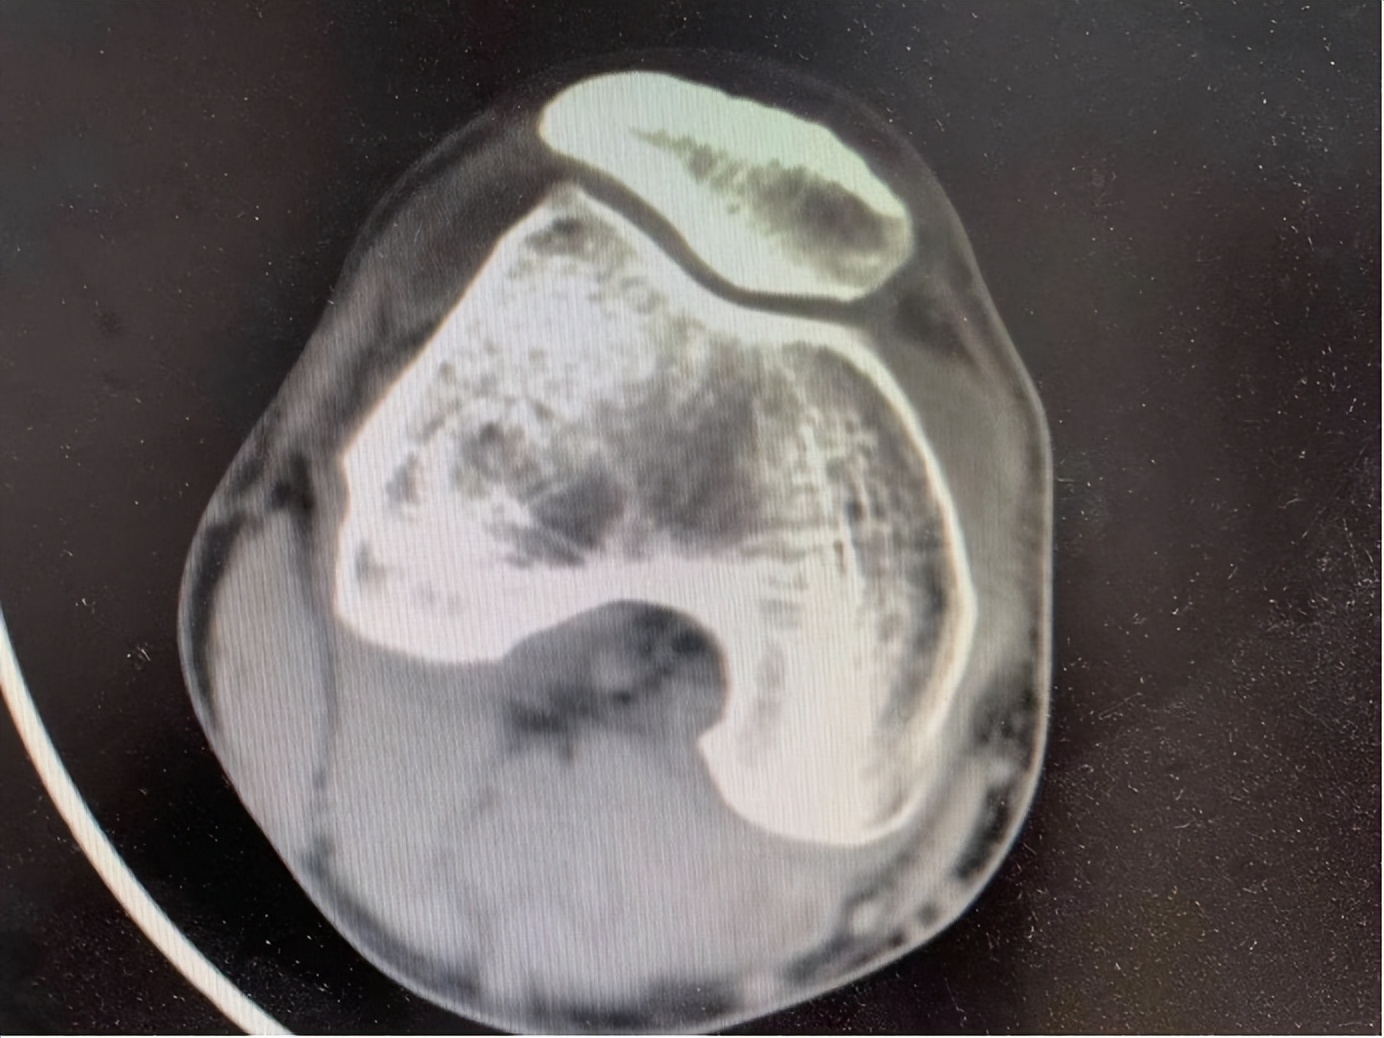

从外观上看,患者右膝关节无肿胀,根据患者描述,走路或者上楼梯时疼痛加重,但痛感不慎,我建议患者做一个右膝关节磁共振,患者表示经济拮据,于是给与右膝关节CT检查:

CT示:患者右膝关节骨质增生,膝关节积液,从患者的症状和描述上看,患者膝关节积液,考虑非菌性炎症。我先验了验患者舌象,苔薄白,舌质淡白,脉象上,沉取有根柢,但浮取较弱,考虑患者体型槁瘦,劳累过度所致。我首先告诉患者,他这种情况,目前不适宜去干活,这段时间必须休息,另外膝关节积液,骨质增生如果中药无法取效,还可以通过针灸加中药治疗,考虑四妙散加减: